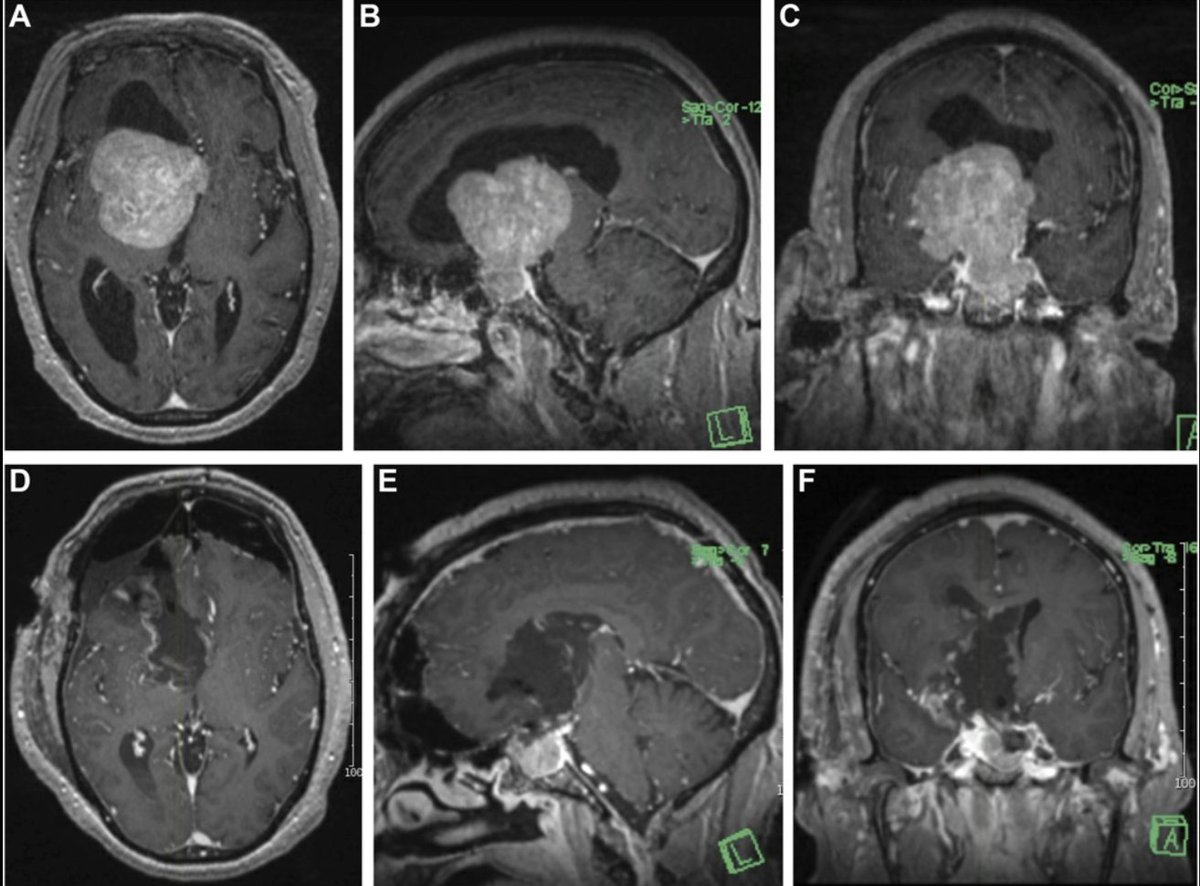

Surgical Strategies in the Treatment of Giant Pituitary Adenomas- Deep dive into the surgical nuances of managing these challenging tumors journals.lww.com/onsonline/abst… #Neurosurgery #nasbs Neurosurgery Publications

#ONSSectionEditorReviewSeries Surgical Strategies in the Treatment of Giant Pituitary #Adenomas bit.ly/3GQ7now by Krishna C. Joshi Rush University System for Health CNS Douglas Kondziolka Mohamed Zaazoue, MD, MSc, MBA Emma Celano Olabisi Sanusi MD, FAANS